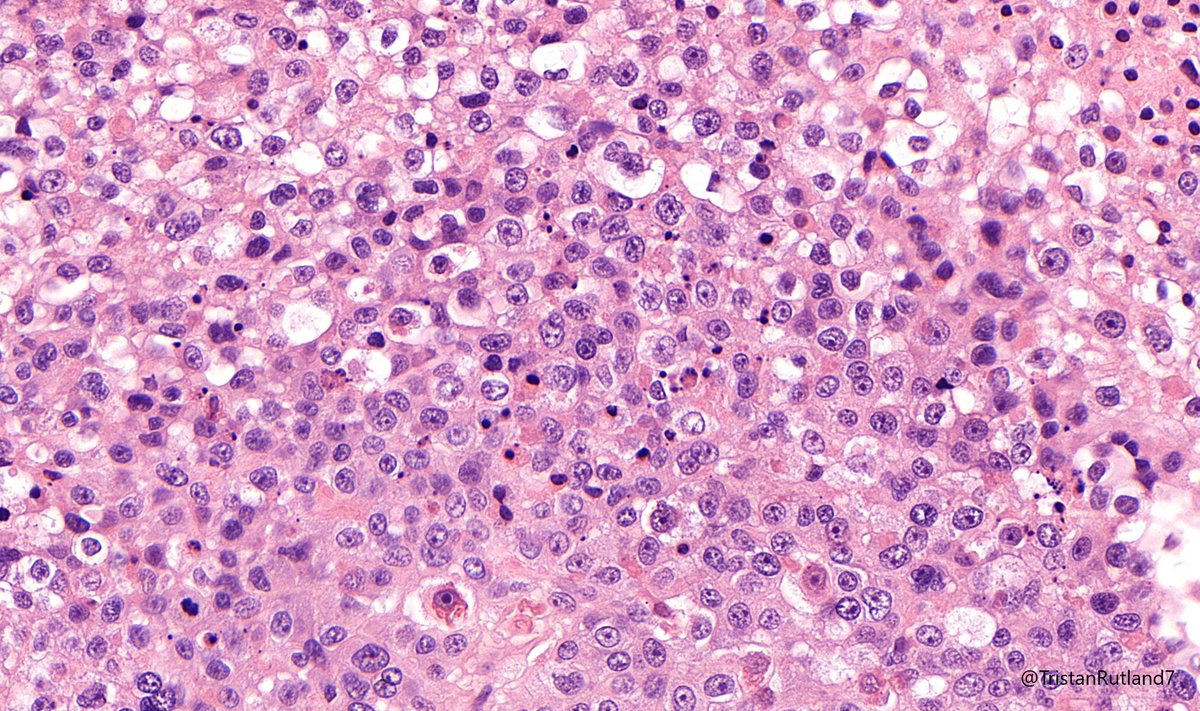

Happy Monday everyone! This is an incidental finding in a reduction mammoplasty. What is your diagnosis? #breastpath #PathTwitter WashU Medicine Pathology & Immunology WashU Medicine Pathology & Immunology Education